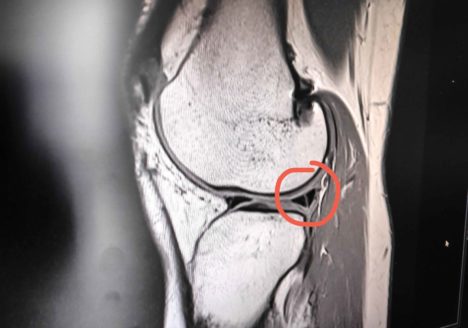

Tagebuch eines Meniskusrisses – Teil 3

Hier kommt also der 3. und hoffentlich letzte Teil meiner Knie-Story. Nach der erfolgreichen Kreuzband OP im Jänner 2020 hatte ich seit Ende August immer wieder Knieschmerzen, die schlußendlich im September als…

Tagebuch eines Kreuzbandrisses – Diagnose Nummer 2

Um meine Knie-Story ein bisschen übersichtlicher zu gestalten folgt nun der zweite Teil. Im 1. Teil habt ihr schon ziemlich viel über meinen Unfall (Anfang Jänner 2020), die Diagnose und die darauffolgende…

Tagebuch eines Kreuzbandrisses – Diagnose, Operation und Reha Teil 1

Ich hab lange überlegt, ob ich einen Blogpost zu diesem Thema schreiben soll. Liest das überhaupt wer? Ich denk mir, wenns nur eine Person liest, die vielleicht in einer ähnlichen Situation ist,…